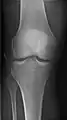

- Knee - AP and Lateral. Intra Condular projections on request

- Patella - Skyline projection

Right knee, anteroposterior

Right knee, lateral

Patella, (slightly skew) skyline